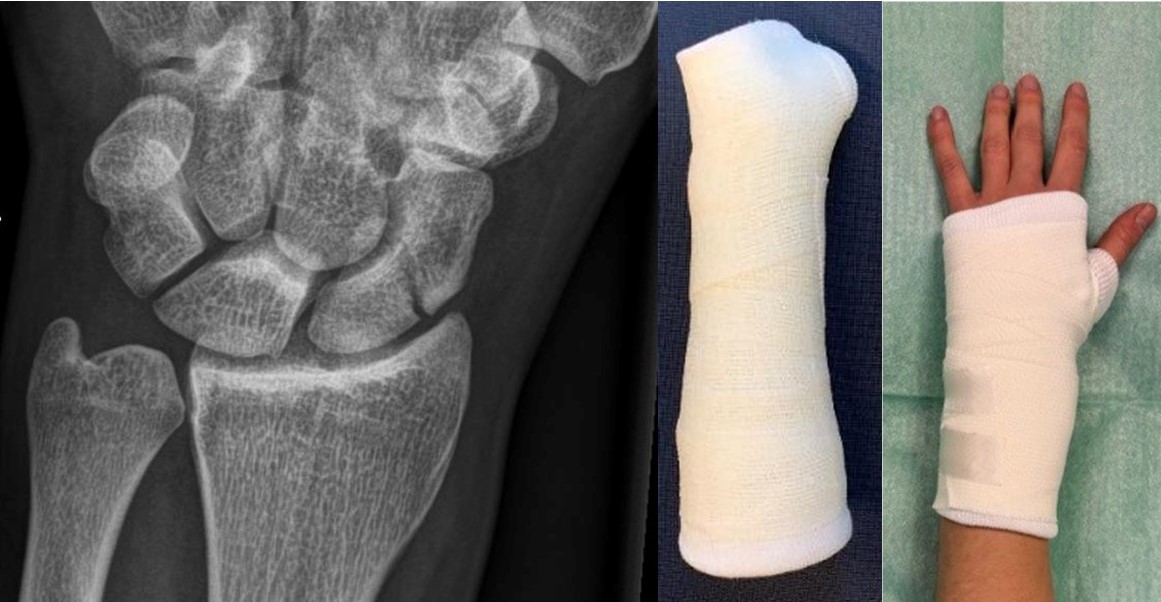

SUSPECT implementation

Clinical suspicion of a scaphoid fracture should be treated initially with a pressure bandage instead of casting.